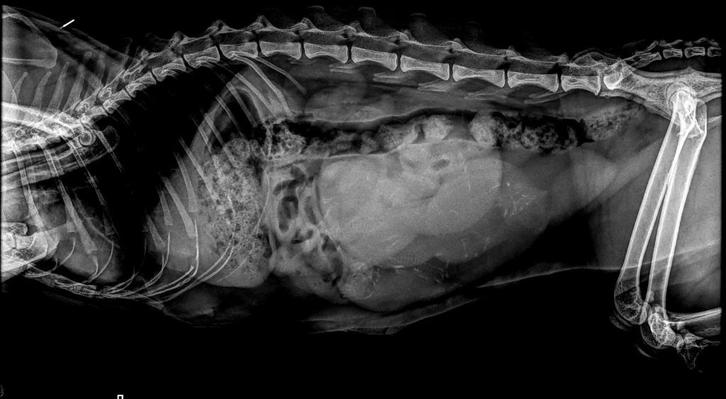

De foto's zijn van eerdere nesten, enkel is de röntgenfoto wel van de nu. Zodra de kleintjes op de wereld zijn en gezond zijn zal ik snel de foto's updaten.